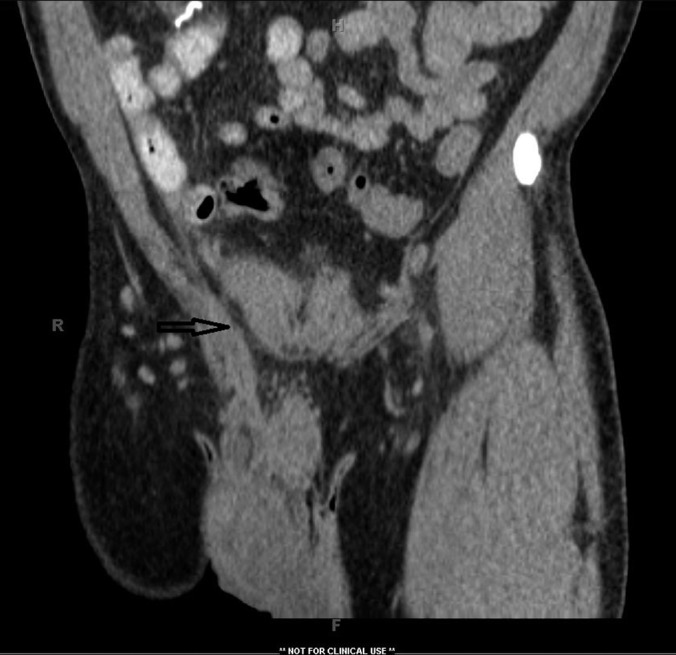

Figure 2.

Coronal view of CT scan of the abdomen and pelvis showing pelvic fluid collection communicating with the right scrotal collection through a patent processus vaginalis.